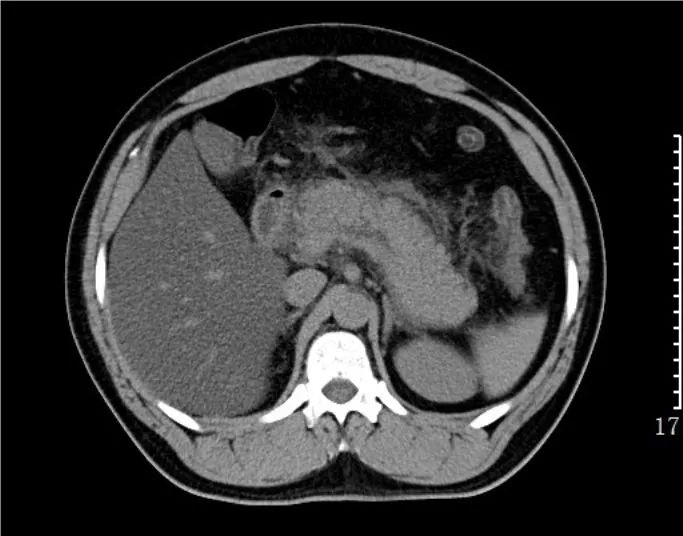

急性水肿型胰腺炎:CT平扫,胰腺明显肿胀,密度尚均匀,周围见条片渗出。

急性坏死型胰腺炎:CT平扫,胰腺密度不均匀减低,胰腺边界模糊,胰腺周围较多渗出积液,肝周可见积液。